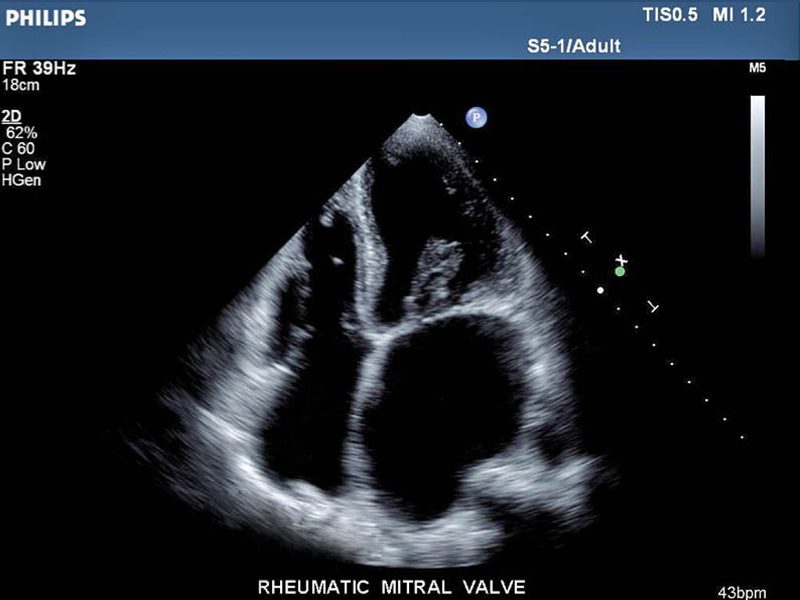

• Para evaluar órganos abdominales y pélvicos.

• Para evaluar condiciones relacionadas con el flujo de la sangre.